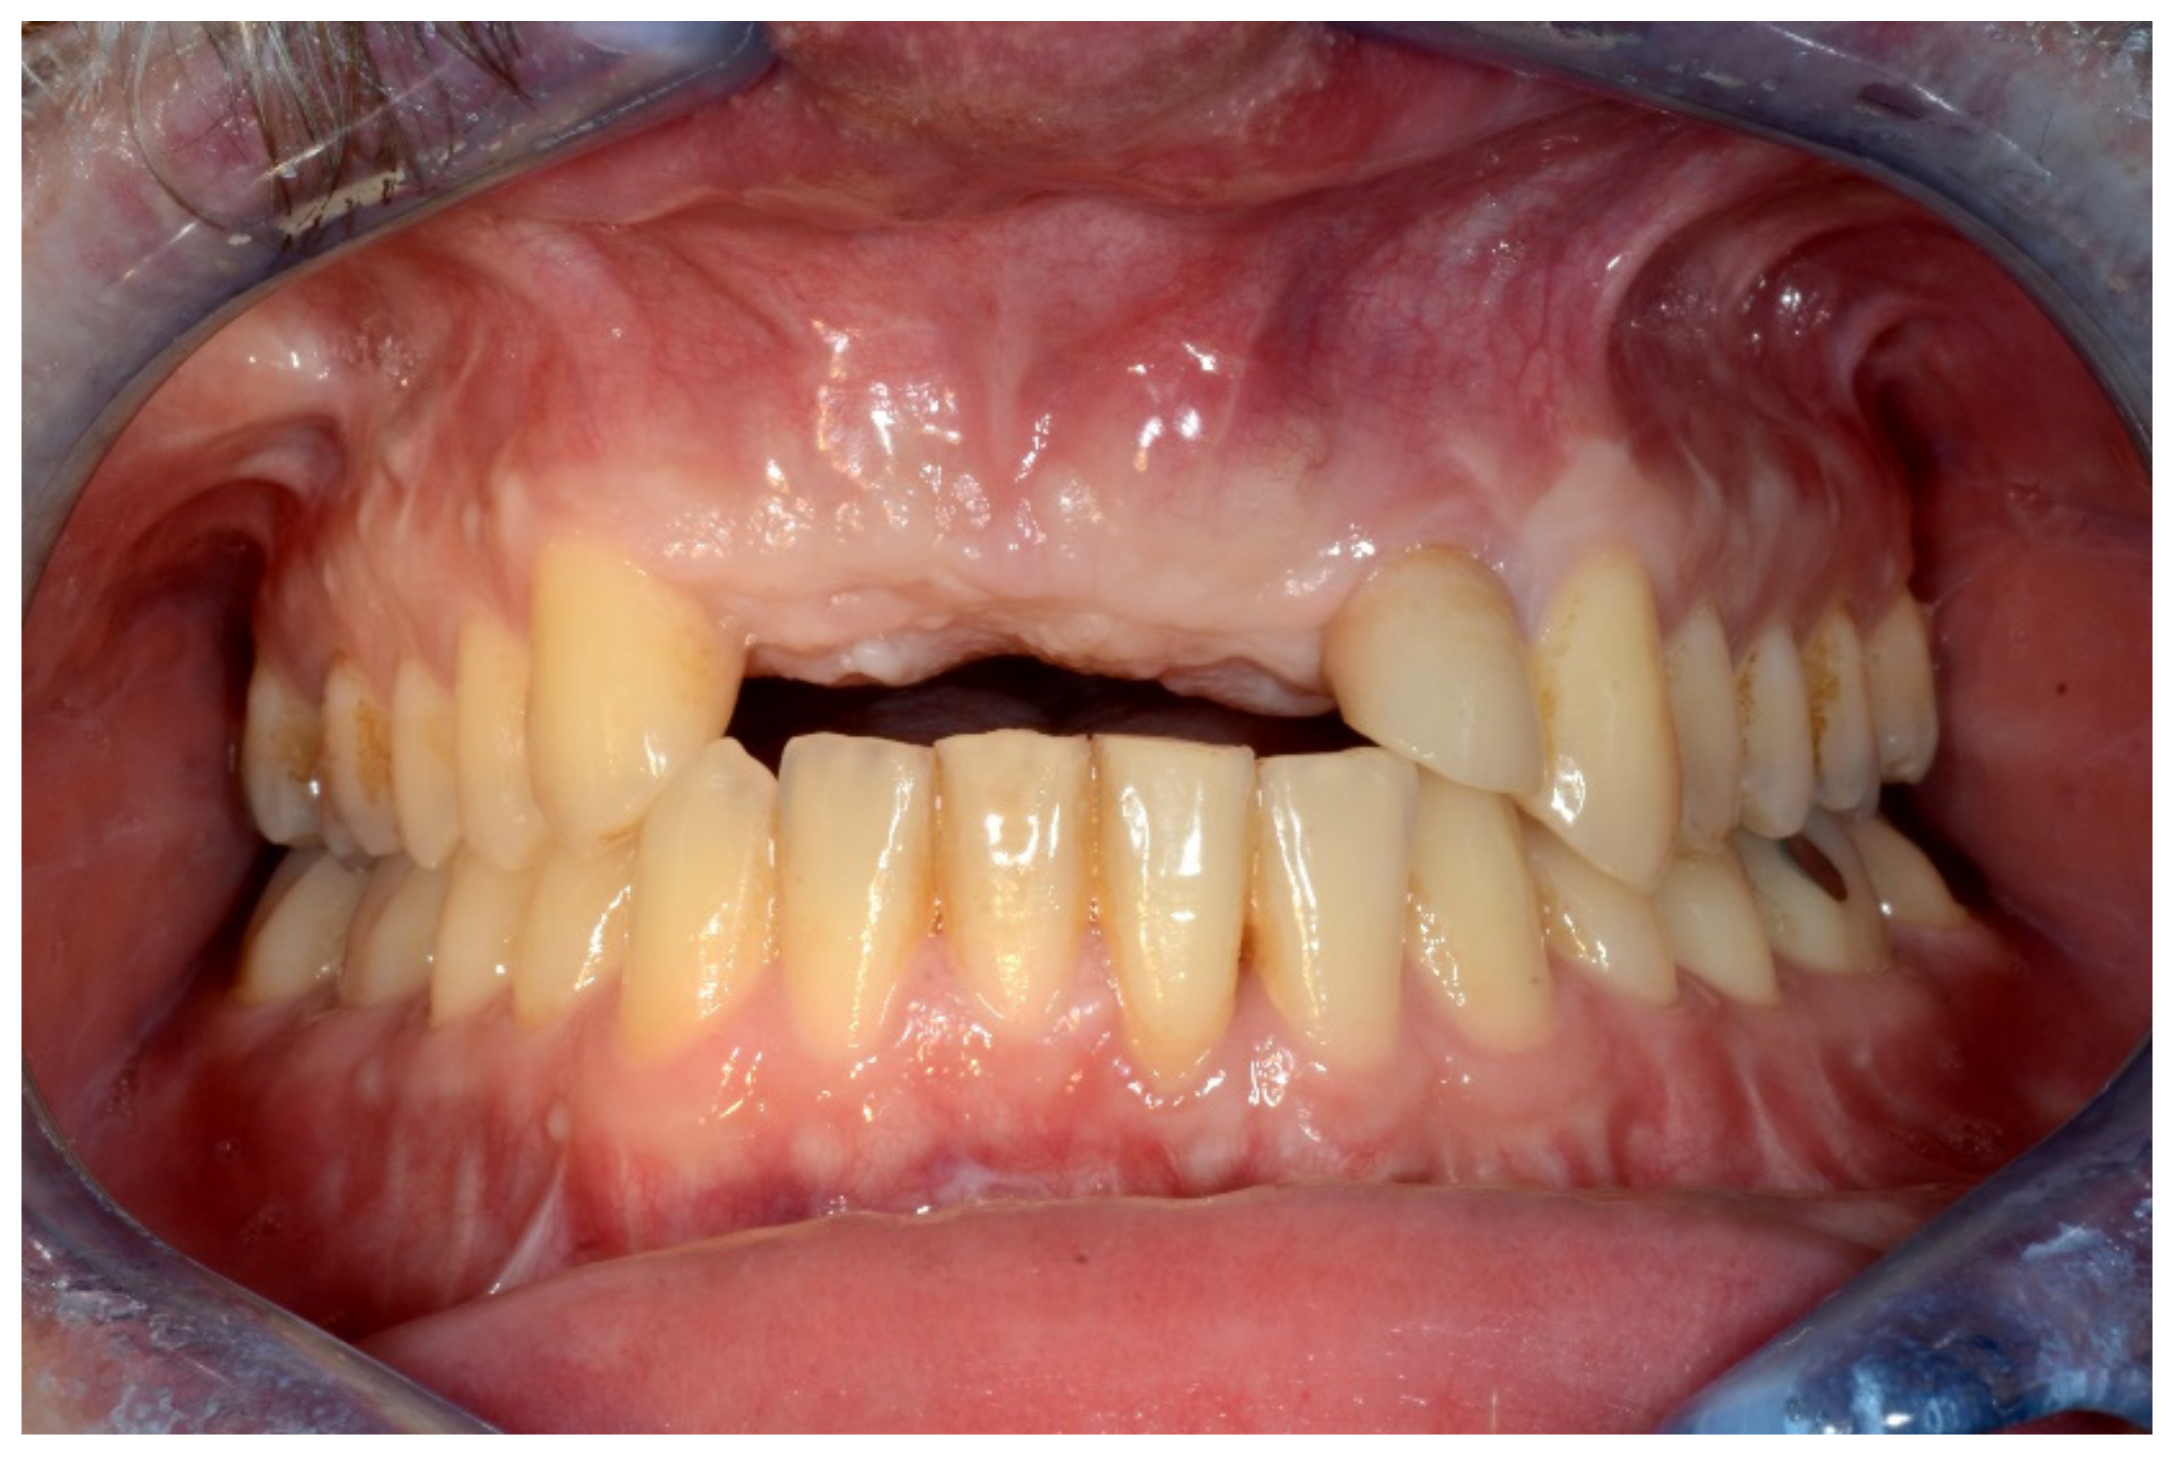

6.3.2. Preoperative Documentation:

However, modification of the residual alveolar ridge due to the reconstructive surgery made the wearing of the previous conventional complete denture impossible. Therefore, rehabilitation using an implant-supported overdenture was planned (Figure 30).

Figure 30.

Intraoral view showing the edentulous defect.